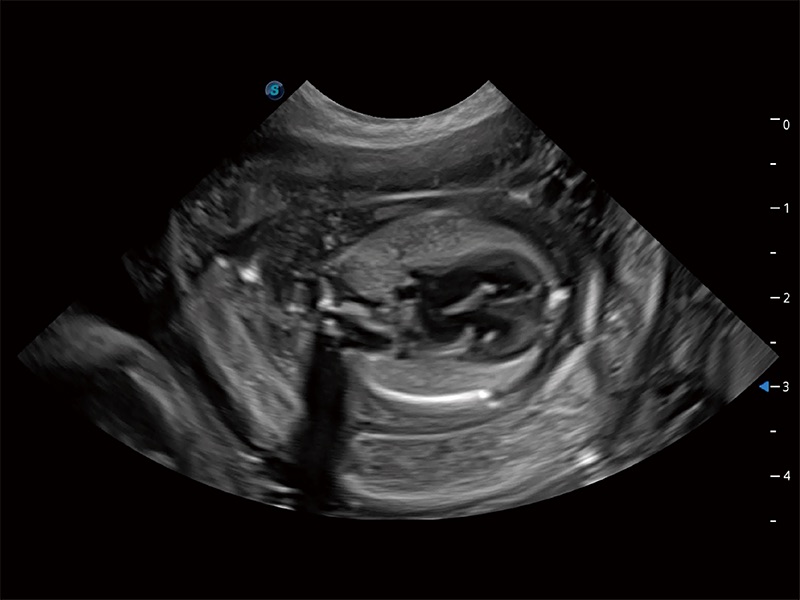

动物是人类最亲密的朋友和最值得信赖的伙伴。百老汇电子游戏官网也一直致力于探索动物专用的超声影像解决方案。全新推出的ProPet系列,是百老汇电子游戏官网在动物超声影像智能化、专业化、精准化的一次跨越式革新。动物不能用言语来表述自己的不适,通过超声影像,ProPet系列搭建了动物医生与不同物种沟通的“桥梁”,为动物医生注入了“治愈之力”。 ProPet 80 是百老汇电子游戏官网匠心打造的一款高端动物专用彩超,采用性能卓越的全新硬件架构,极大提升超声系统的运行效率和数据处理能力,帮助动物医生从容应对日益增多的挑战性病例和日益多样化的临床需求。

高性能和先进的临床应用工具可以为动物医生提供临床信心。ProPet 80 搭载了先进的腹部和浅表应用工具,帮助医生在日常临床实践中发挥前所未有的作用。

ProPet 80 专为动物医生设计,对不同的动物体型和生理结构作出了针对性的优化。通过动物影像专用软件,可满足个性化的应用需求,帮助动物医生获得更精确的诊断数据。